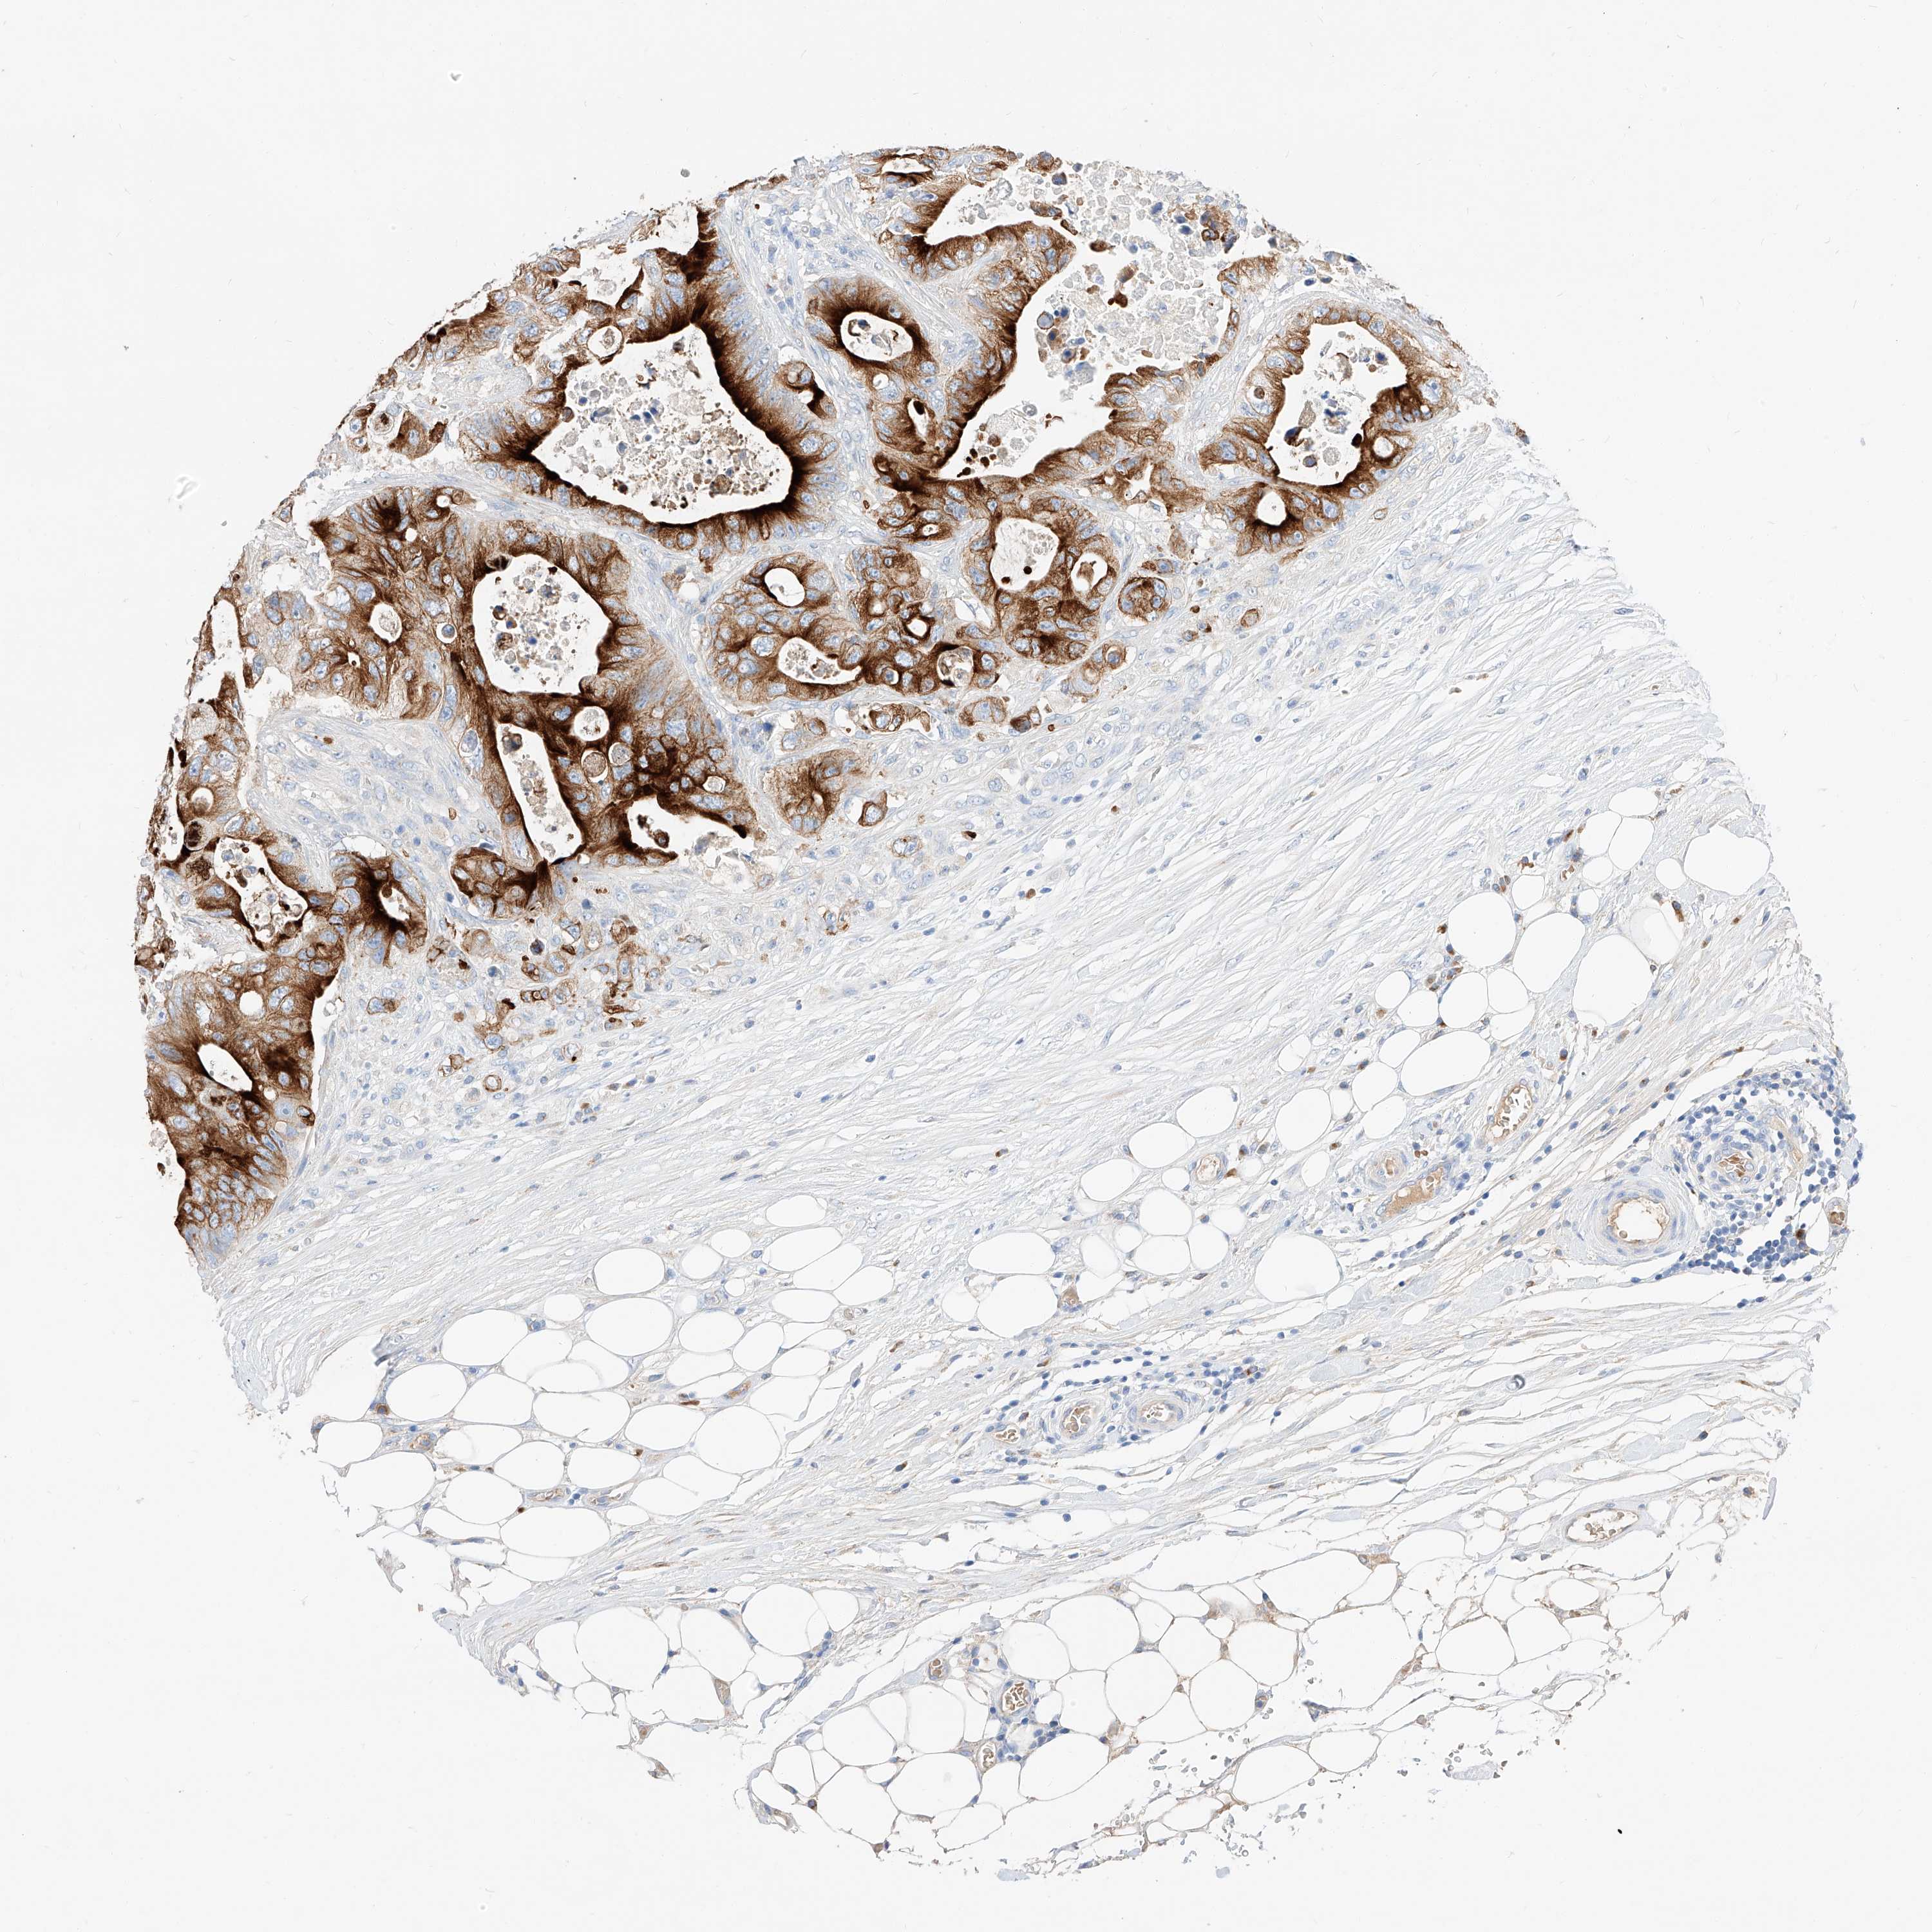

CANCER COLORECTAL CANCER Show tissue menu

Colorectal cancer

Human cancer

Colon adenocarcinoma